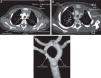

Angio-TAC con contraste: cortes sagitales a nivel de la aorta ascendente-transversa, siguiendo la tráquea. A) Se aprecia el nacimiento de los 2 arcos desde la aorta ascendente y cómo rodean la tráquea, siendo el derecho el dominante (correspondencia con la imagen 1A). B) Imagen radiológica del «anillo» completo con el arco derecho dominante respecto al izquierdo. C) Reconstrucción coronal desde visión posterior, en la que se aprecia la bifurcación de aorta ascendente con supraaórticos «en espejo», saliendo los 2 del lado derecho desde el arco derecho, que es dominante (algo mas grueso) y los 2 del lado izquierdo del arco aórtico izquierdo, que es de menor calibre.